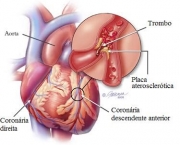

Ataque cardíaco ocorre quando uma artéria coronária se torna bloqueadas de modo simultâneo. O bloqueio repentino rouba certa porção do músculo do coração e fornecimento vital do sangue. De fato acontece a morte do músculo. O bloqueio súbito da artéria coronária é causada por ruptura de placa na artéria que produz variedade de condições clínicas, incluindo ataques cardíacos e angina instável, agrupados sob o nome de síndrome coronariana aguda (SCA). Todas as formas de SCA são emergências médicas, tratados com medicamentos, angioplastia, implante e cirurgia para restaurar o fluxo normal de sangue através da artéria bloqueada. Se o fluxo pode ser restaurado dentro de poucas horas, danos permanentes podem ser minimizados.

Infarto do miocárdio resulta da interrupção parcial do fornecimento de sangue a uma parte do músculo cardíaco, fazendo com que as células do coração sejam danificadas até morrer. Isto acontece em geral devido à oclusão (bloqueio) de uma artéria coronária após a ruptura da placa aterosclerótica vulnerável, conjunto estável de colesterol, ácidos gordos e os glóbulos brancos do sangue na parede da artéria. Resultante de isquemia (restrição no fornecimento de sangue) e consequente falta de oxigênio. Caso deixada sem tratamento por um período de tempo suficiente pode causar danos ou morte (infarto) do tecido muscular do coração (miocárdio). Os sintomas típicos de infarto agudo do miocárdio incluem súbita dor no peito (geralmente irradia para o braço esquerdo ou do lado esquerdo do pescoço), falta-de-ar, náuseas, vômitos, palpitações, sudorese e ansiedade. As mulheres podem experimentar sintomas típicos menores do que os homens, caso da falta de ar, fraqueza, sensação de indigestão e fadiga. Proporção considerável de infartos do miocárdio (22-64%) “silenciosa”, isto é, sem dor no peito ou outros sintomas. Entre os testes de diagnóstico para a detecção de danos ao músculo cardíaco estão: Eletrocardiograma (ECG), ecocardiograma e vários exames de sangue. Os marcadores utilizados com frequência são de creatina e fração dos níveis de troponina.

- Transmural: Associado com a aterosclerose envolvendo a artéria coronária principal. Prolongam-se através de toda a espessura do músculo cardíaco. Representa resultado da oclusão do fornecimento de sangue da região.

- Subendocárdica: Envolve pequena área na parede subendocárdica do ventrículo esquerdo, septo ventricular ou músculos papilares. A área é susceptível à isquemia.